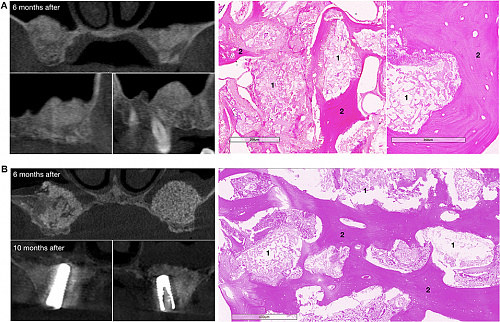

Опубликованы результаты клинических исследований первого в мире ген-активированного материала

Проведены успешные клинические исследования первого в мире ген-активированного материала для наращив...